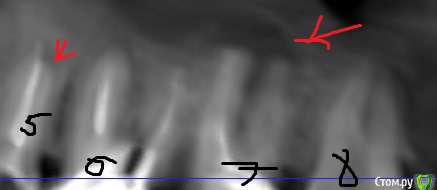

klemento Опубликовано 30 сентября, 2019 Поделиться Опубликовано 30 сентября, 2019 (изменено) Здравствуйте. Прощу помощи, т.е. совета. Проблемы слева вверху. После лечения 6 зуба и дальнейшего его протезирования вкладкой и коронкой - появилась боль при накусывании в области 5-6 зуба. Появляется преимущественно после жевания и попадания пищи. Знакомый посоветовал сделать КТ. Я обратился в 3 клиники. В 1 мне сказали удалить 6 и 7, т.к. что-то пошло в пазуху(снимок пазухи), там видно в виде пятна серого, а так же на 4 и 5 делать резекцию, т.к. выведен материал за верхушку. В двух других - сказали попытаться вскрыть 7 зуб, т.к. не понятно, что там с ним - может и получиться спасти, а 6 - не трогать(мол как простоит так простоит) . Про 5 ничего сказать не могут. Так же на 4 что-то есть и про него ничего не сказали.Хотелось бы понять как поступить. Возможно ли сохранить 7 зуб и действительно ли не трогать 6, но тогда ходить с воспалением? На одном из снимков есть двойка протезированная - на ней воспаление уже несколько лет и не беспокоит - трогать ее или делать резекцию? Понимаю, что дурак раз запустил так зубы, но обидно, что много денег отдал на 6 зуб и теперь под удаление его... Хотелось бы услышать какие-то варианты. Заранее спасибо. Изменено 30 сентября, 2019 пользователем klemento Ссылка на комментарий

krokomot Опубликовано 3 октября, 2019 Поделиться Опубликовано 3 октября, 2019 Вот КТ. Только надо вручную ссылку копировать, а то из форума не открывает.https://dropmefiles.com/1aSGrА что делать с воспалением под запротезированном зубом? Врачи снимать коронку и вкладу не хотят браться.Томограмма отвратительная, то что по ней удалось определить что в 7м не запломбирован дистальный канал, лечение перепломбировка, нужен еще прицельный снимок коронок 6-ого и 7ого, из-за наводок невозможно определить состояние тканей вокруг этих коронок и особенно в промежутке между 6-м и 7-м, в 5м выведения материала нет, в 4-м есть 0.5 мм это не критично никакие резекции делать не нужно, по поводу 2-ки лечите канал и переставляйте коронку. для обьективной картины нужна хорошая томограмма на современном томографе типа Sirona, и прицельные снимки 5-й,6-й,7-й зубы на визиографе с позиционером, а не пальцем датчик держать. Скорее всего все зубы спасабельны, но это не точно)) Ссылка на комментарий

klemento Опубликовано 4 октября, 2019 Автор Поделиться Опубликовано 4 октября, 2019 Томограмма отвратительная, то что по ней удалось определить что в 7м не запломбирован дистальный канал, лечение перепломбировка, нужен еще прицельный снимок коронок 6-ого и 7ого, из-за наводок невозможно определить состояние тканей вокруг этих коронок и особенно в промежутке между 6-м и 7-м, в 5м выведения материала нет, в 4-м есть 0.5 мм это не критично никакие резекции делать не нужно, по поводу 2-ки лечите канал и переставляйте коронку. для обьективной картины нужна хорошая томограмма на современном томографе типа Sirona, и прицельные снимки 5-й,6-й,7-й зубы на визиографе с позиционером, а не пальцем датчик держать. Скорее всего все зубы спасабельны, но это не точно))Спасибо огромное за ответ. Обнадежили. Подскажите пожалуйста, а в 5 верхней обычно 2 канала или 1? Мне его вскрыли заложили кальций. Но он что-то на перкуссию и накусывание всё равно реагирует. Может там всё таки не могут найти 2 канал? Ссылка на комментарий